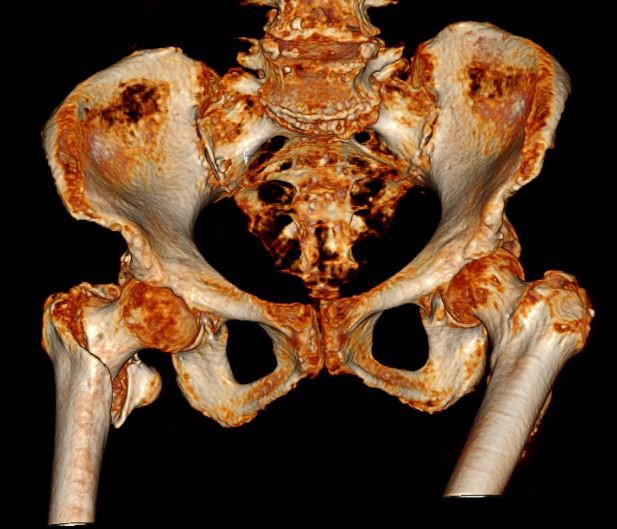

适逢疫情封控期间,近百岁的杨奶奶在家中不小心从凳子上滑倒,导致左髋部疼痛,无法活动,辗转来到东方医院南院。在急诊外科就诊,行CT扫描后诊断为“右侧股骨转子间骨折”。由于患者年龄较大,存在心律失常、肺动脉高压、慢性阻塞性肺病等基础性疾病,手术风险极大。但是,如果不进行手术治疗选择保守治疗呢?选择保守治疗可能意味着患者生命即将走到终点,因为老年髋部骨折保守治疗预后不理想,致残率和病死率较高,据统计,一半以上的患者会丧失生活自理能力,12%~20%的髋部骨折患者会在1年内死亡,因而老年髋部骨折被称为“人生的最后一次骨折”。骨折本身并不致命,但是长期卧床会导致压疮、下肢深静脉血栓、肺栓塞、肺部感染、泌尿系统感染等多种并发症,每种并发症都会致命。在患者家属权衡手术治疗与保守治疗的利弊后,出于对东方南院急诊创伤外科的信任,选择手术治疗。